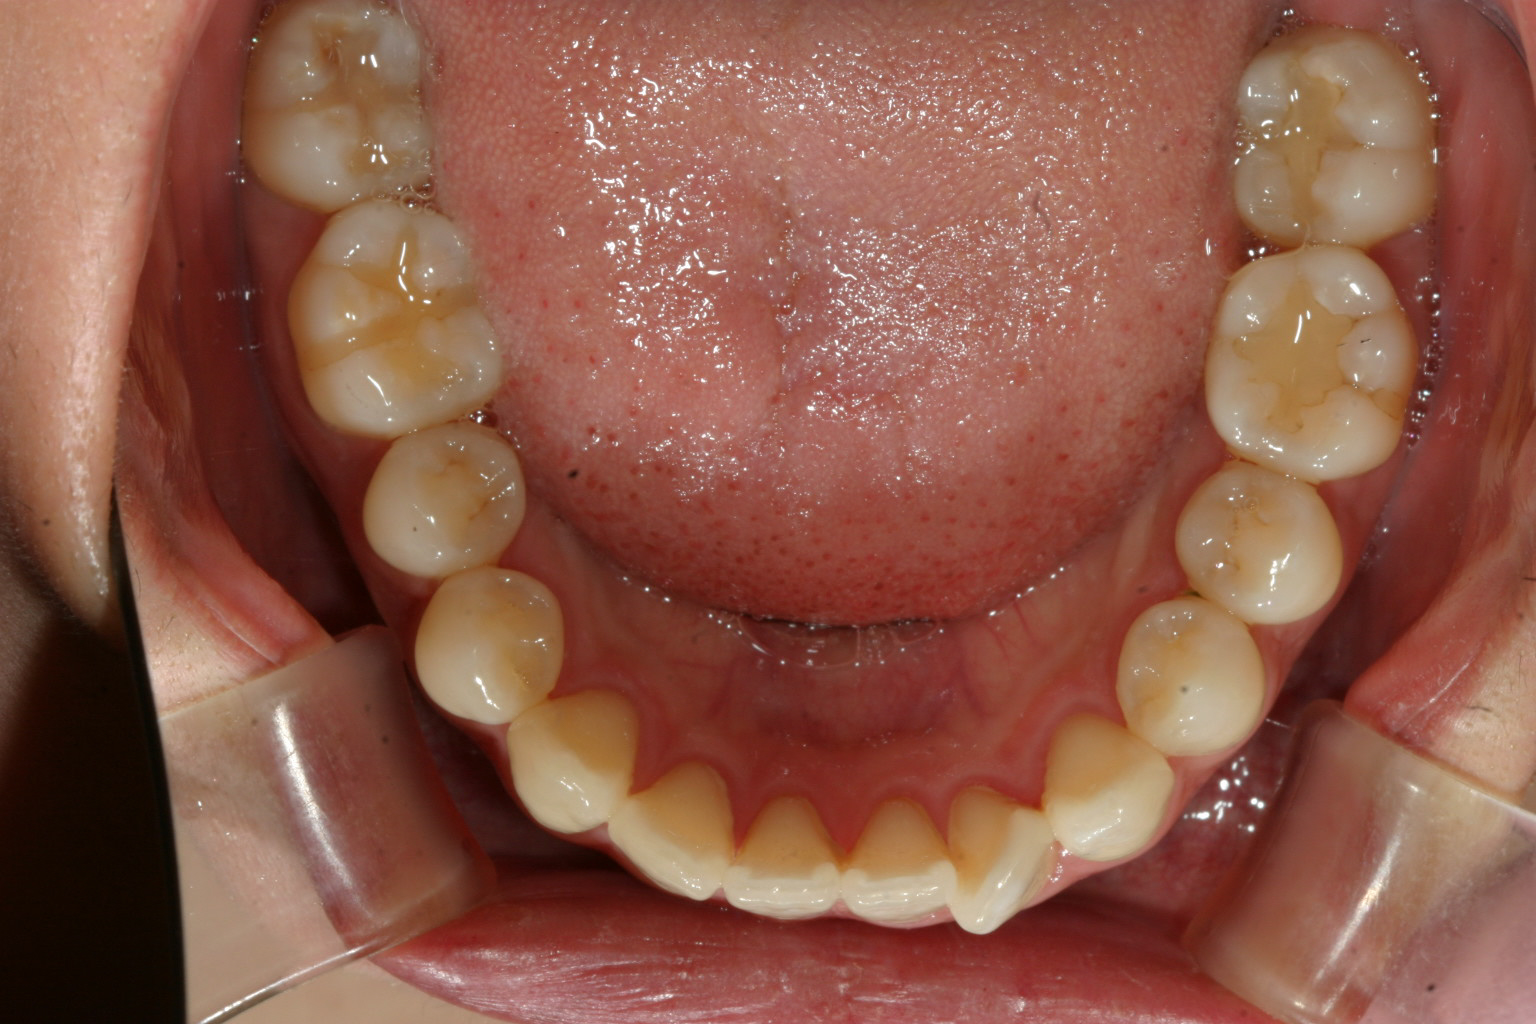

少し前歯が翼状捻転してますがそんなに悪くないですね~

全体的に綺麗な歯列ですが1歯だけ気になりますね~

少し受けてますね~ 上顎の歯列もさほど乱れがなく受け口と言うのは少し厄介でガタガタなら綺麗に並べれば全体的に歯列は前に出ますが、綺麗な歯並びだと前には出てくれません。